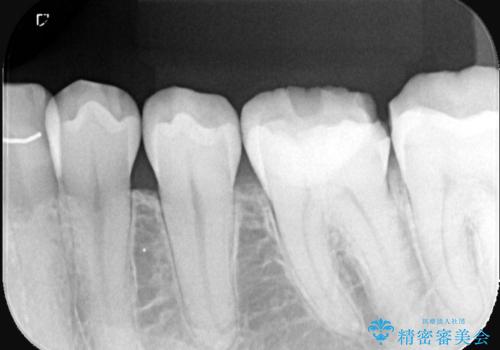

- 主訴:強く噛んだら歯がポロポロ欠けてきた。

左下6番目の歯の咬合面にプラスチックの材料が詰まっており、歯質がドーナツ状にしか残っていなかったため、歯質幅が比較的薄かった場所が欠けてしまったようでした。

今後の破折リスクを説明し、セラミッククラウンでのやり替えとなりました。

頬舌的レジンインレーが入っており、歯質幅の薄かった且つ強く咬合していた遠心側歯質が欠けてしまっていました。また新しい窩洞のインレーを入れても、近心側歯質の破折のリスクは抱えたままになることから、クラウンでの修復をおすすめし審美性・適合性のよいセラミッククラウンでのやり替えとなりました。